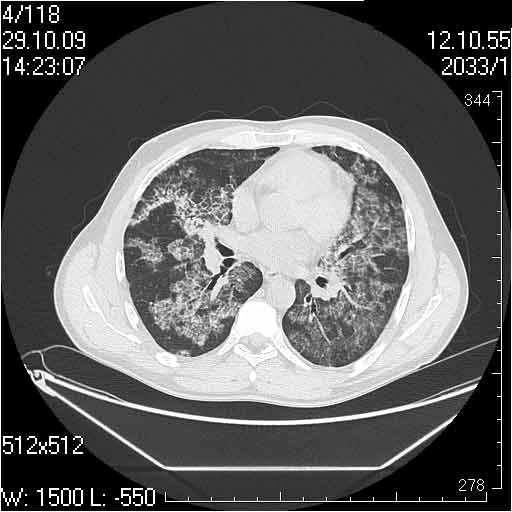

Случай №3

Женщина 51 год

Случай 3:смешанные изменения; подходят для интерстициальной пневмонии, тактика аналогична случаю 1.